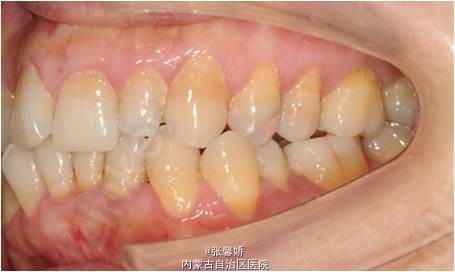

上中线右偏1mm,A2、D4反合,A2、B2畸形牙偏小,拥挤度上颌4mm、下颌6mm。Spee曲线:左侧3mm,右侧2.5mm

牙列中度拥挤;A2、D4反合 处理:时代天使隐形矫治器矫治 拔除C8、D8 适当下前牙邻面去釉 排齐整平上下牙列,改正A2、D4反合 治疗时间2年左右,矫治后牙齿排列整齐,咬合关系良好,患者满意。

一年后随访,患者咬合关系仍稳定,尖窝锁结良好。 隐形矫治适应证的选择很重要,适合中低难度的成人病例,患者的配合和依从性要求较高。 此患者术前全景片可见多个充填物,为龋易感患者,而且牙周也不是很好,隐形矫治没有拖槽更利于患者口腔卫生的维护,防止龋病的发生和牙周病的加重。